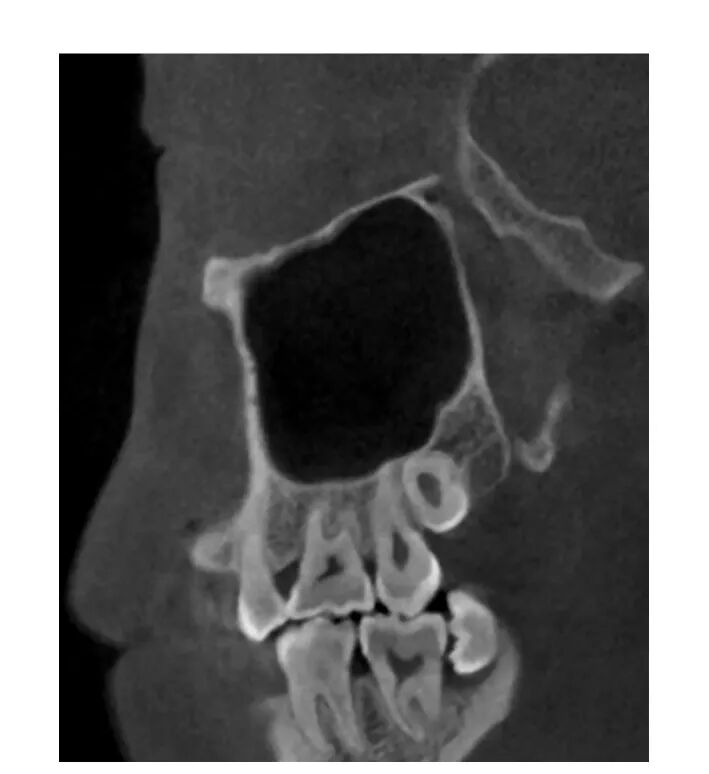

上颌窦内的分隔是窦壁骨质的突起,呈隆起状、锯齿状或棘状(图1-1-19),分隔上附有薄的窦黏膜。有学者认为该结构可分为原发性和继发性,原发性分隔可能跟牙齿的发育和萌出有关,而继发性分隔可能是牙缺失后上颌窦气化引起窦底壁形态的改变。分隔的发生率约从13%~35. 3%不等,高度约为2. 5~12. 7mm。

CBCT矢状位示上颌窦内不同形状的分隔,呈隆起状、锯齿状或棘状